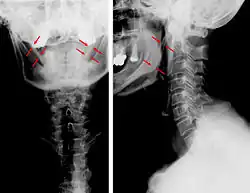

| Anteroposterior and lateral radiographs of cervical spine showing ossification of the stylohyoid ligament on both sides | |

-

Radiograph, lateral view showing elongated stylohyoid process and stylohyoid ligament ossification -

Radiograph, lateral view showing joint-like formation in ossified stylohyoid ligament -

CT scan, coronal section showing bilateral extended styloid process and stylohyoid ligament ossification (incidental finding) -

Imaging is important and is diagnostic. Visualizing the styloid process on a CT scan with 3D reconstruction is the suggested imaging technique.[13] The enlarged styloid may be visible on an orthopantogram or a lateral soft tissue X ray of the neck.